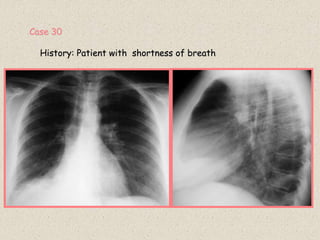

Case 30

History: Patient with shortness of breath

.

For detailed description of lobar collapse

see slide 61.